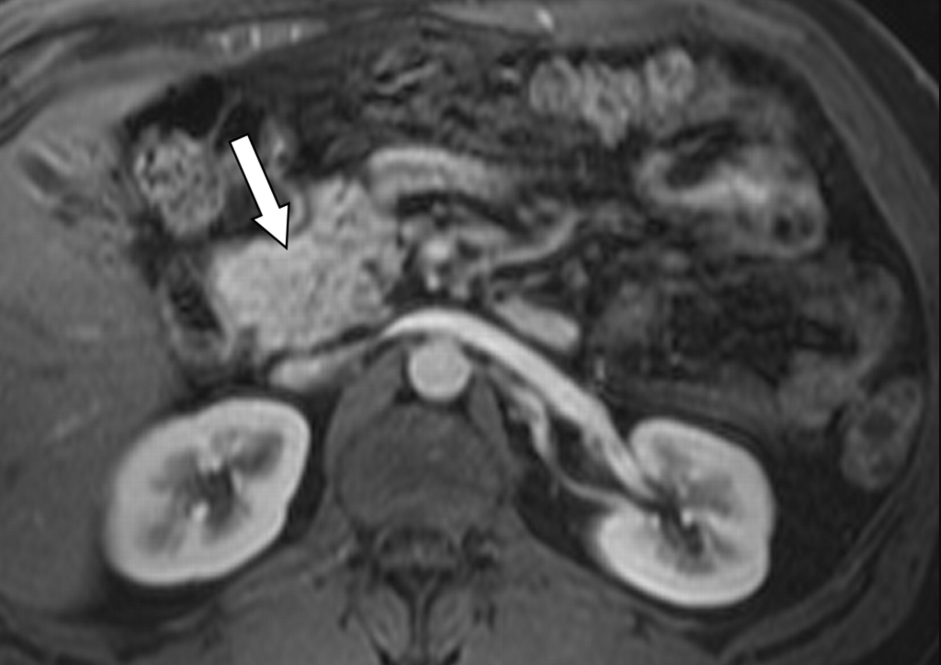

胰腺癌的诊断依赖于影像学检查和病理学检查。

常见的诊断方法包括超声波检查、计算机断层扫描(CT)、磁共振成像(MRI)和内窥镜检查等。尽管这些检查有助于发现肿瘤的存在。

但早期的胰腺癌通常很难通过这些方式被及时发现,尤其是当肿瘤位于胰腺深部或体积较小时。